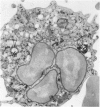

The morphology and function of cytoplasmic lipid bodies in human neutrophils were evaluated. By transmission electron microscopy, neutrophil lipid bodies were cytoplasmic inclusions, usually several microns in diameter, that occasionally coalesced to attain a diameter up to 7 microM. Neutrophil lipid bodies were not enveloped by membrane but were often surrounded by a more electron-dense shell at their periphery. Normal peripheral blood neutrophils contained an average of approximately one lipid body per cell. Lipid bodies appeared in greater numbers in neutrophils from inflammatory lesions. Perturbation of neutrophils during conventional methods of cell isolation and purification modestly increased lipid body numbers in neutrophils, whereas incubation of neutrophils with 1 microM oleic acid rapidly induced lipid body formation over 30 to 60 minutes. After granulocytes were incubated for 2 hours with 3H-fatty acids, including arachidonic, oleic, and palmitic acids, electron microscopic autoradiography demonstrated that lipid bodies represented the predominant intracellular sites of localization of each of the three 3H-fatty acids. There was lesser labeling noted in the perinuclear cisterna, but not in cell membranes. Virtually all of each of the three 3H-fatty acids incorporated by the neutrophils were esterified into chromatographically resolved classes of neutral lipids or phospholipids. These findings indicate that cytoplasmic lipid bodies are more prominent in neutrophils in vivo engaged in inflammatory responses and that these organelles in human neutrophils function as sites of deposition of esterified, incorporated fatty acids.